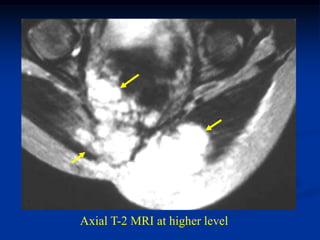

Axial T-2 MRI

Axial T-2 MRI at higher level

femur

tumor